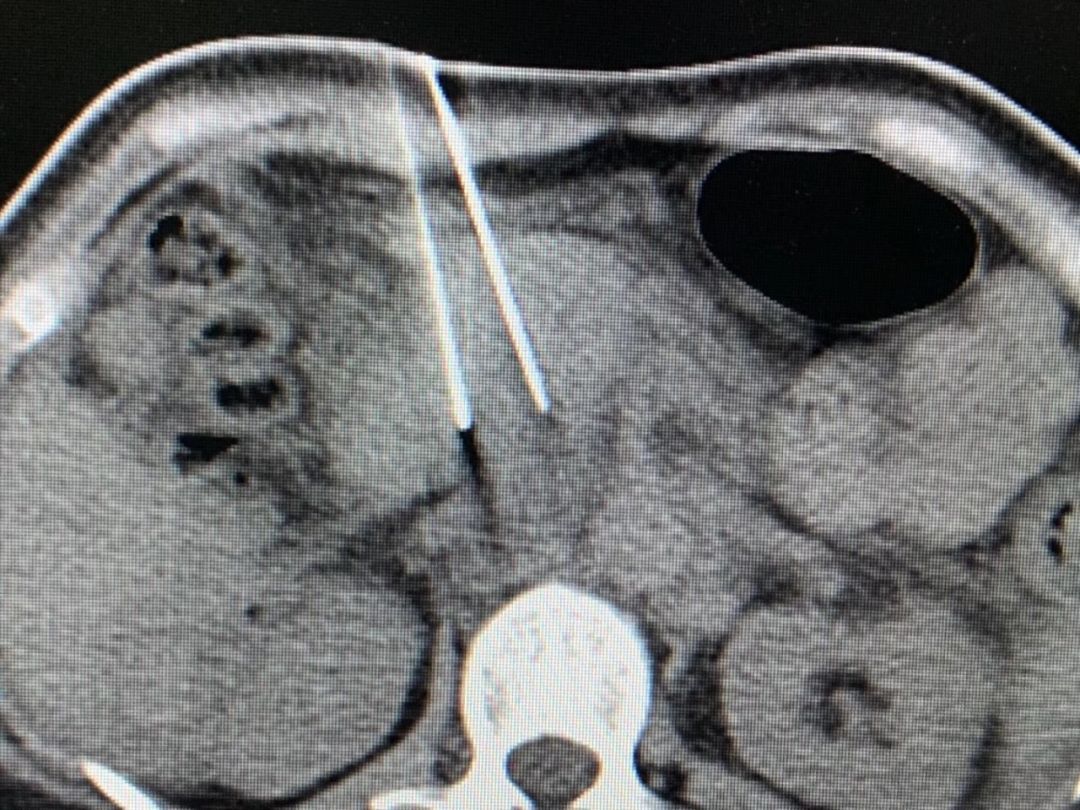

目前,消融都是在影像引導(dǎo)下來做的,比如CT,超聲,磁共振都是一個平面。這樣是兩個維度去看腫瘤,對于腫瘤的全貌就看得不夠仔細。就像是我們看一個人,在照片上與視頻里的效果是完全不一樣的。我們現(xiàn)在的CT片,就相當于看一個腫瘤的照片,而不是立體的。所以在腫瘤消融中,要重建很多照片,需要依靠醫(yī)生在腦海中把照片組合起來來才能判斷有沒有完全把腫瘤看清晰,對醫(yī)生經(jīng)驗的依賴性非常強。

我們知道,3D技術(shù)在醫(yī)學中運用得越來越多。如果在消融中能夠應(yīng)用3D技術(shù),把一些未清晰的,不夠明確的腫瘤通過3D技術(shù)展現(xiàn)出來,讓醫(yī)生能夠清晰立體的看到腫瘤的位置,大小和周圍器官的關(guān)系,特別是血管,神經(jīng),腸道,這些組織肯定會看的非常清晰。如果這個技術(shù)被應(yīng)用到臨床,那么手術(shù)將會變得更加安全。